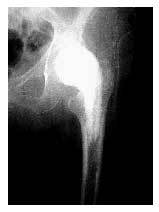

* Radiografía anteroposterior de la cadera (fig. 10).

Figura 10. Radiografía estándar anteroposterior, postoperatoria, de la cadera.